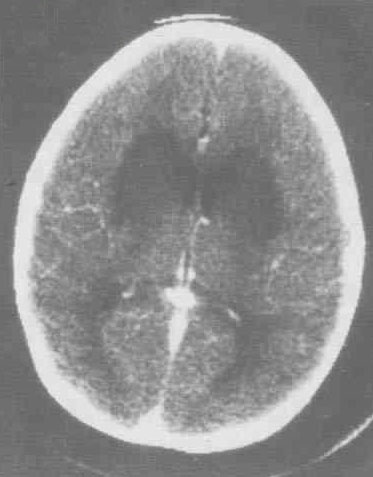

腦炎是指腦實質(zhì)受病原體侵襲導(dǎo)致的炎癥性病變,是腦實質(zhì)受病原微生物直接侵犯所引起的炎性改變,絕大數(shù)的病因是病毒,也可由細(xì)菌、霉菌、螺旋體、立克次氏體、寄生蟲等感染引起,有的可能是變態(tài)反應(yīng)性疾病,如急性播散性腦脊髓炎。那么腦炎的早期癥狀有哪些呢?

腦炎的病因有很多,但是大多數(shù)都是由于病毒引起。病毒性腦炎是指由多種病毒,引起的顱內(nèi)急性炎癥。由于病原體的不同和宿主反應(yīng)過程的差異,會形成不同類型的表現(xiàn)。